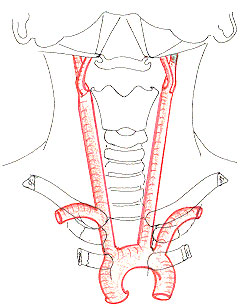

Lartre vertbrale irrigue la portion postrieure de lencphale et en partie la moelle.

Elle se dtache de la sous-clavire la hauteur de la premire vertbre thoracique; elle rejoint le plan vertbral, monte travers les canaux transversaires partir de C6 ou C5 jusquՈ la charnire, traverse le triangle musculaire de Tillaux et passe dans la fosse postrieure en empruntant un interstice entre les ligaments occipito-atlodiens. Elle contourne en spirale le flanc du bulbe, monte contre sa face ventrale et se termine en regard du trou borgne en sanastomosant avec son homologue en formant le tronc basilaire. Son calibre ne dpasse pas 4mm.

-1: Tronc brqchio-cphalique gauche

-2: A. carotide primitive

-3: A. sous-clavire

-4: tronc thyro-bicervico-scapiulaire

-5: A. vertbrale

Ce parcours, bien plus long que celui de la carotide, traverse quatre rgions:

- elle occupe au niveau du creux sus-claviculaire le trigone vertbral dont le sommet est reprsent par lapophyse transverse de C6 (repre de Chassaignac) ;

- la veine vertbrale, plexiforme, et le nerf vertbral laccompagnent dans la traverse du canal tranversaire :

- Sa traverse des parties molles de la charnire occipito-vertbrale sinscrit dans le triangle de Tillaux ;

- la jonction mdullo-bulbaire, elle croise par-devant les racines mdullaires du nerf spinal (XI) dont elle est spare par le ligament dentel, puis se dirige vers le sillon mdian du bulbe en croisant le nerf hypoglosse (XII), lolive et la pyramide bulbaires, pour atteindre enfin le niveau du trou borgne.

Ses collatrales intracrniennes irriguent :

- la dure-mre de la fosse postrieure (artre mninge postrieure);

-       le bulbe (artres du corps restiforme, artre olivaire) ;

-       la moelle (artres spinales antrieure et postrieure)

- la face infrieure du cervelet par lartre crbelleuse infrieure et postrieure (PICA), important repre smeiologique en radiographie.